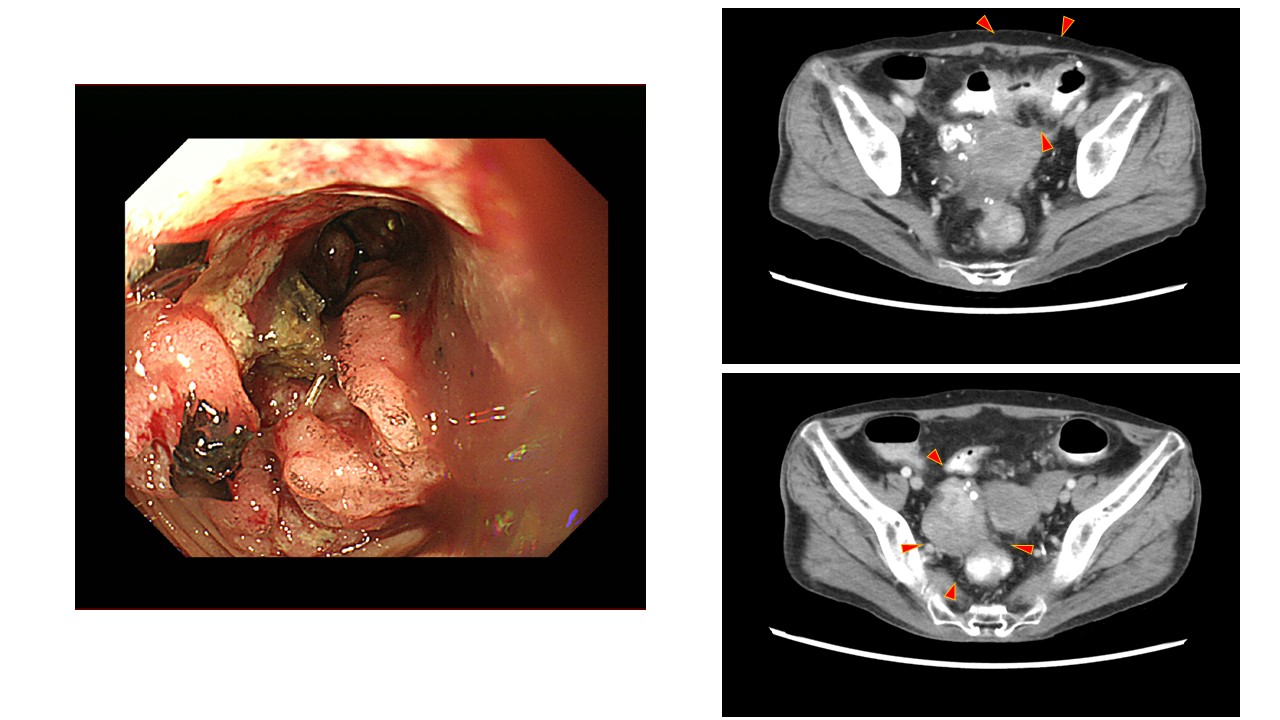

Colonoscopy revealed a circumferential ulcerative mass. The biopsied specimen was moderately differentiated adenocarcinoma. Computed tomography showed a wall-thickening of the sigmoid colon and an ovarian mass 6 cm in diameter (Figure 1). We were unable to determine if the ovarian mass was primary or metastatic pre-operatively. A laparoscopic sigmoidectomy and bilateral adnexectomy were performed. Intraoperatively, we found an infiltrative and indurated appendix (Figure 2), and an enlarged right ovary, and some white nodules in the pouch of Douglas (Figure 3), which were considered to be ovarian and appendiceal metastases and derived from sigmoid colon cancer. Therefore, appendectomy was also performed during the scheduled procedure. Postoperative histopathology revealed sigmoid colon adenocarcinoma with TNM classification of pT3N1aM0 and appendiceal GCA with metastasis to the ovary. Peritoneal dissemination was not confirmed histopathologically; however, we judged it was derived from appendiceal GCA according to its characteristic proclivities by manifestations of gynecological tract metastases and peritoneal spread. The resected specimen of the sigmoid colon was composed of moderately differentiated adenocarcinoma diffusely positive for cytokeratin (CK20) and negative for CK7, chromogranin, and synaptophysin (Figure 4).

Figure 1

Figure 1. Colonoscopy showed an ulcerative tumor in the sigmoid colon (left). Computed tomography revealed wall thickening in the sigmoid colon (right, upper) and an irregularly shaped mass in the right ovary (right, lower).